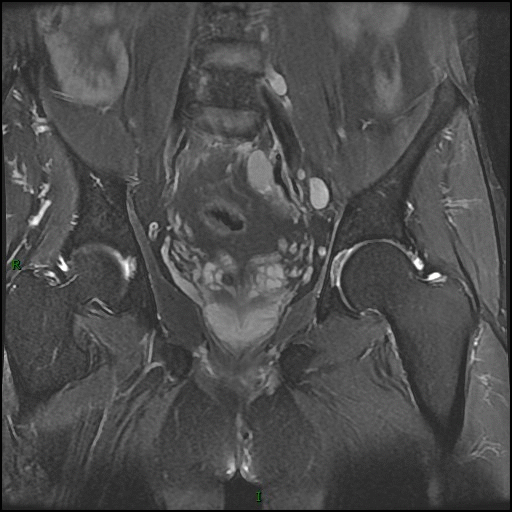

MR 平扫及增强

依据:病灶大,骨质破坏同时突破骨皮质于骨旁形成软组织肿块,骶骨形态存在。病灶骨质破坏相对较轻,而软组织肿块明显。MR 平扫病灶信号均匀,未见明显坏死成分。增强后病灶明显均匀强化。病灶周围可见肿大淋巴结,增强后肿大淋巴结明显均匀强化。

PBL 的 MR 表现:病灶以 T1WI 低或等信号、T2WI 等信号为主,偶呈高信号(细胞排列紧密,水分少),T2WI 压脂呈高信号。淋巴瘤常形成体积较大的软组织肿块,位于椎体者常包绕椎体,并常常累及椎管,因硬膜具有一定阻挡作用,故肿块多位于椎管内硬膜外,可包绕椎管四周生长,形成「袖套」或「肉包骨」样改变。增强肿块一般轻中度均匀强化,坏死囊变少见。